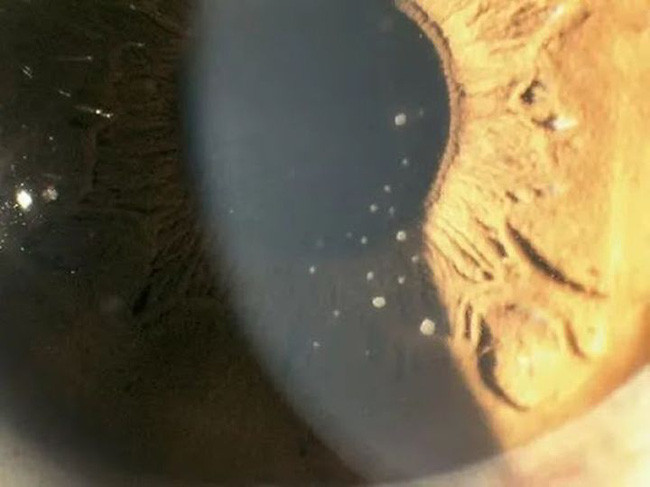

Bác sĩ kiểm tra cho Tiểu Khiết phát hiện IOP (áp lực nội nhãn) ở mắt phải của cô cao tới 55mmHg (IOP bình thường là 10-21mmhg), kết mạc của mắt phải xung huyết nhẹ, phù nề biểu mô giác mạc, và một số cặn lắng được nhìn thấy ở phía sau giác mạc, Tiểu Khiết được chẩn đoán là bệnh tăng nhãn áp .

Hình ảnh một số cặn lắng được nhìn thấy phía sau giác mạc